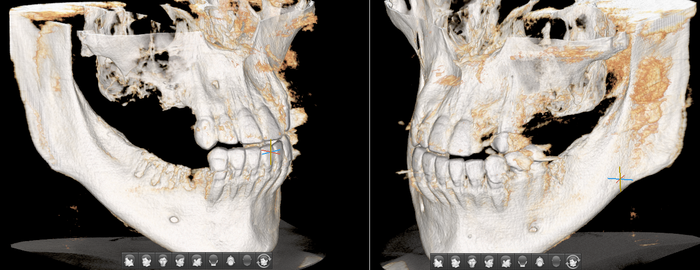

Согласитесь, не особо эстетично. Ортопантомограмма:

Фрагмент компьютерной томографии (вид сбоку):